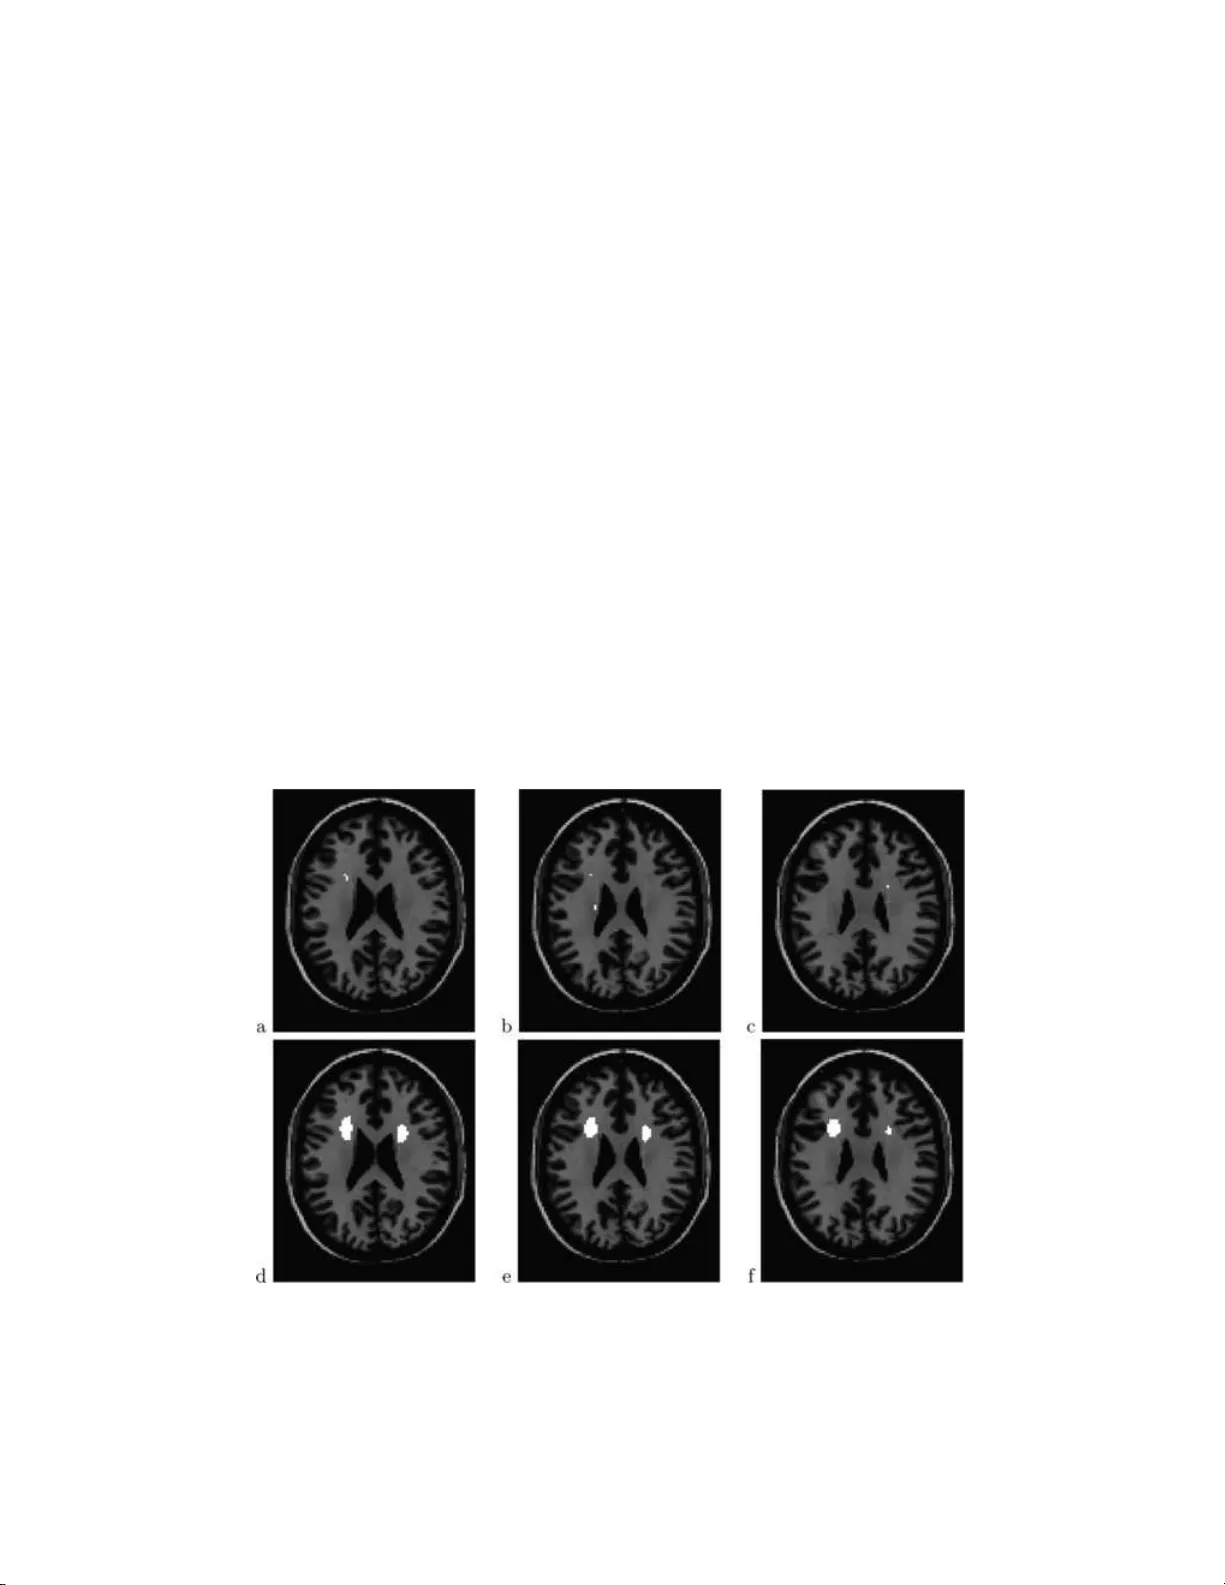

The Annals of Applie d Statistics 2008, V ol. 2, No. 1, 153–175 DOI: 10.1214 /07-A OAS133 c  Institute of Mathematical Statistics , 2 008 F ALSE DISCOVER Y RA TE ANAL Y S IS OF BRAIN DIFFUS ION DIRECTION MAPS By Armin Sch w ar tzman, 1 R ob er t F. Dougher t y 2 and Jona than E. T a ylor 3 Harvar d Scho ol of Public He alth , Stanfor d Univ ersity and Stanfor d University Diffusion tensor imaging (DTI) is a nov el modality of magnetic resonance imaging that allow s noninv asive mapping of th e brain’s white matter. A particular map derived from DTI measuremen ts is a map of water principal diffusion directions, whic h are proxies for neural fib er directions. W e consider a study in which d iffu sion direc- tion maps were acquired for t wo groups of sub jects. The ob jective of the analysis i s to find re gions of the brain in whic h the cor respond - ing d iffusion directions differ b etw een the groups. This is attained by first computing a test statistic for the difference in direction at every brain location using a W atson model for d irectional data. In- teresting lo cations are sub sequently selected with contro l of the false disco very rate. More accurate mo deling of the null distribu t ion is obtained using an emp irical n ull d ensit y bas ed o n the empirical dis- tribution of the test statistics acros s th e brain. F urth er, substantial impro vemen ts in p o wer are achiev ed by lo cal spatial ave raging of t he test statistic map. Alth ough the focus is on one p articular study and imaging tec h nology , the proposed inference metho ds can be applied to other large scale sim ultaneous h yp othesis testing problems with a conti nuous un derlying spatial structure. 1. Int r o duction. A cen tr al statistical p roblem in brain imaging s tu dies is to find areas of the b rain that differ b et ween t wo groups of sub jects, namely , a con trol group and another group with a sp ecial c haracteristic of in terest. Diffusion tensor imaging (DTI) is a mo dalit y of MRI that allo ws insigh t into Received Ap ril 2007; revised Ap ril 2007. 1 Supp orted in p art by a William R. and Sara Hart Kim ball Stanford Graduate F ellow - ship. 2 Supp orted by t h e Sch wab F oundation for Learning a nd N I H Gran t EY-01-5000 . 3 Supp orted by N SF Grant DMS-04-05970. Key wor ds and phr ases. Diffusio n tensor imaging, directional statistics, multiple test- ing, empirical n ull, spatial smo othing. This is an electronic reprin t of the original article published b y the Institute of Mathema tical Sta tistics in The Annals of Applie d Statist ics , 2008, V ol. 2, No. 1, 153– 175 . This reprint differs from the original in pag ination and t yp ographic detail. 1 2 A. SCHW A R TZMAN, R. F. DO UGHER TY AND J. E. T A YLOR the brain’s wh ite matter. As opp osed to fun ctional MRI, wh ich shows b rain activit y , DTI rev eals anatomical structure. DTI measures th e d iffusion of w ater molecules in tissu e [ Bammer et al. ( 2002 ), Basser and Pierpaoli ( 1996 ) and Le Bihan et al. ( 2001 )]. S ince the m o v emen t of wa ter is affected by the cell structure, the pattern of diffusion is an indicator of the microscopic prop erties of the tissue. DTI d ata differ fun damen tally from con ven tional imaging d ata in that v alues at eac h sp atial lo cation are n ot scalars b u t 3 × 3 p ositiv e definite matrices, also called diffusion tensors (DTs). T he DT at a lo cation in sp ace can b e th ough t of as the co v ariance matrix of a 3D Gaussian distribution that mo dels the lo cal Brownian motion of the w ater m olecules in that lo cation. The DTs are measured at discrete v olum e elemen ts called v oxe ls arranged in a r egular spatial grid. V o xels are t ypically ab out 2 mm in size. A typica l DT image of the entire b rain ma y conta in a few h u ndred thousand vo xels. Because of familiarit y with scalar statistics, inv estigators fr equen tly re- strict their analysis of DTI data to scalar quant ities d eriv ed from the DT [e.g., Bammer et al. ( 2000 ) and Deutsc h et al. ( 2005 )]. Th e tw o most imp or- tan t s u c h qu antites are trace and fractional an isotropy (F A), b oth fun ctions of the DT’s eigen v alues related resp ectiv ely to the total amount of d iffusion and the degree of anisotrop y within a vo xel. The most imp ortan t nonscalar quan tit y derive d from the DT is the pr incipal diffusion direction, defined as the eigen v ector corresp ondin g to the largest eigen v alue of th e DT. It is generally assum ed that diffu sion is r estricted in the d irection p erp endicu- lar to the nerv e fib ers, so the principal diffusion direction provides a proxy for the fib er dir ection within the v oxe l [ Le Bihan et al. ( 2001 )]. Thus, in- ference ab out the principal diffusion direction is v aluable for und erstanding where in the brain d ifferen t neural fib er s may b e dir ected to. Th e other t wo eigenv ectors are not as easily inte rpretable. F ortu n ately , there is a ric h literature in directional statistics that can help with this pr ob lem. T o the b est of our kn o wledge, the first attempt to formally analyze p rincipal dif- fusion direction maps in a m ulti-sub ject stu dy has b een rep orted by th e authors [ Sc hw artzman et al. ( 2005 )]. The present article is an extension of the analysis rep orted there. Giv en t w o s ets of principal diffusion direction maps, the task at hand is to find regions that d iffer b et wee n the tw o groups. After app ropriate spatial registration so that all images are aligned in the s ame co ordin ate system, the analysis can b e b rok en down into t wo main steps : (1) Computation of a statistic that tests the difference b et wee n group mean d irections at ev ery v oxe l; (2) In f erence on th e o ve rall test statistic map. F or step one, we use a pr obabilit y mo del for the principal d iffusion direc- tion giv en by the bip olar W atson distribution on the un it sphere [ Best and Fisher ( 1986 ), Mardia and Ju pp ( 2000 ) and W atson ( 1965 )]. W e c hose this d istri- bution b ecause it is one of th e simplest that p ossesses the p rop ert y of b eing FDR ANA L YSIS O F BRAIN DIFFU SION DIRECTION MAPS 3 an tip o dally symmetric, giving to eac h direction and its negativ e the same probabilit y . Th is is crucial b ecause the DT is inv arian t u nder sign changes of the p rincipal eigen vec tor. Th is particular mo d el leads to appropr iate defini- tions of mean direction an d disp ers ion f or a random samp le of directions, as w ell as a test s tatistic for testing w h ether tw o samples of directions, that is, same v o xel across t wo groups of su b jects, ha ve the same mean. According to this mo del, the test statistic u nder the null hyp othesis has an approximat e F distribu tion for fix ed sample size, asymptotically as the samples b ecome more concen trated around th eir mean. This is usefu l wh en the n u m b er of sub jects is small, as it is generally the case in imaging studies. The second step in the analysis corresp onds to solving a m u ltiple testing problem among a large n u m b er of v oxe ls. F or this we use the pro cedure by Storey , T a ylor and Siegmund ( 2004 ) that con trols the false discov ery rate (FDR). FDR inference has b een applied su ccessfu lly to microarra y analy- sis [e.g., Efron et al. ( 2001 ) and Ef ron ( 2004 )], but is still a relativ ely new tec hnique in b r ain imaging [Geno vese, Lazar and Nic hols ( 2002 ) and Pac i- fico et al. ( 2004 )], where, in con trast, the usu al approac h has b een cont rol of the family-wise error rate (FWER) usin g Gaussian random field theory [ W orsley et al. ( 1996 )]. A p ractical reason for our c ho osing FDR o ve r FWER is that the Storey , T a ylor and Siegm un d ( 2004 ) p ro cedure dep ends only on the marginal distribution of the test statistics, wh ile FWER con tr ol would require knowledge of the co v ariance prop erties of the random field d efined b y th e test statistics. Th is is relev an t b ecause the marginal distribution of the W atson statistic is easy to estimate, while the field prop erties are not. A metho dological reason for usin g FDR is that sometimes researchers are not so interested in cont rolling the error o ver the en tire searc h region b ut rather findin g interesti ng r egions that could b e further inv estigate d. F or this reason it is appr opriate to use the con v entio n in tr o d uced b y Efron ( 2004 ) of calling the selected vo xels “in teresting.” The inno v ativ e asp ects of the statistical analysis are tw ofold. The first is a new empirical null for global mo d eling of the test statistic. Since the num b er of sub j ects is s mall, a parsimonious m o del (su c h as the W atson) is needed at eac h vo x el. On the other hand, the n u m b er of vo xels is large, so more accurate mo deling of the n ull distribution of the test statistic can b e ob- tained by considering global parameters common to all vo xels. These global parameters are fi t based on the emp irical distr ib ution of the test statistic among v oxels that ma y b e considered to b elong to the null class. Th is em- pirical null concept was originally sugge sted f or z -scores in a microarra y exp eriment setting [ Efron ( 2004 )]. W e introd uce here a new version of the empirical n u ll adapted to the F nature of the W atson test statistic. The second innov ativ e asp ect is the increase of p ow er in FDR in ference through s p atial smo othing. An imp ortant d istinction b et wee n the multiple testing p roblems in brain imaging and microarray analysis is that the former 4 A. SCHW A R TZMAN, R. F. DOUGH ER TY A ND J. E. T A YLOR are accompanied by a spatial stru cture. W e tak e adv anta ge of this p r op ert y to increase statistica l p o wer b y applying lo cal spatial a ve raging, whic h re- duces the noise v ariance. While routinely used in image pro cessing, the effect of sp atial smo othing on FDR inference is only starting to b e studied [P aci- fico et al. ( 2004 )]. Here the empirical null helps again assess the marginal n u ll distr ib ution of the test statistic after smo othing. The article is organized as follo ws. S ection 2 describ es the d ata. S ection 3 , together with the App endix , summarize the r elev an t features of the W atson distribution. S ection 4 describ es the FDR inferen ce, including the empirical n u ll and th e lo cal av eraging. Th e data analysis is integrat ed into Sections 3 and 4 and follo w s along w ith th e theory . F urther ev aluation and criticism of the analysis results are offered in Section 5 . 2. The data. Our p articular dataset concerns an observ ational study of anatomical differences related to reading abilit y in c hildr en, condu cted by a research team at Stanford Universit y that included one of th e authors (RFD). Th e study w as motiv ated by a pr evious rep ort of anatomical evi- dence of d yslexia in adults [ Klin b erg et al. ( 2000 )]. Two groups of c h ildren w ere recru ited for the stud y: a con trol group consisting of children with nor- mal reading abilities and a case group of c hildr en with a pr evious diagnosis of dyslexia. The sub jects we r e ph ysically and mental ly health y , strongly righ t-hand ed, 7–13 y ears of age, h ad English as their p rimary language and in telligence within the a verage range. There were no significan t group dif- ferences in age, gender, parent al education or so cio economic status. More details on the study and the image acquisition are giv en in Deutsc h et al. ( 2005 ). The data set consists of 12 diffusion direction maps, of wh ic h 6 b elong to the control group and 6 to the d yslexic group. Eac h d iffu sion direction map is a 95 × 79 × 68 array of vo xels representi ng spatial lo cations in a rectangular grid with 2 × 2 × 3 mm regular spacings. T o ev ery v oxe l corresp onds a un it v ector in R 3 that indicates the principal diffus ion direction at that vo xel. These vecto r s actually rep r esen t axes in the sense th at the vecto r s x and − x are equiv alen t. F or th e pur p oses of statistical analysis, all diffu sion direction maps are assumed to b e aligned in the same co ordinate system so that eac h v o xel corresp onds to the same b rain stru ctur e across all sub jects. Since sub jects ha ve differen t head sizes and shap es and ma y lie slightly differen tly in the scanner, co-registrat ion of the im ages was necessary . The common co ordi- nate system used here is a standard called the MNI template. The vertica l z axis corresp onds to the inferior-su p erior dir ection for a sub ject s tanding u p, lo oking forwa r d. T he origin is lo cated at an anatomical land mark lo w near the cen ter of the br ain called the an terior commissure. In br ief, for eac h su b- ject, b oth linear an d nonlinear trans f ormation p arameters we re compu ted FDR ANA L YSIS O F BRAIN DIFFU SION DIRECTION MAPS 5 from that sub j ect’s scalar MRI intensit y image by min imizing the squ are error difference b et ween th e transf ormed image and the template. The DTs w ere then inte rp olated en try w ise in the transformed grid and p rincipal d if - fusion directions w ere recompu ted from the DTs at the n ew lo cations. The principal d iffu sion directions w ere then reorien ted b y applying the lin ear p ortion of the transf ormation and renormalizing to un it length. F or m ore details on this pr o cess, s ee Sc hw artzman, Doughert y and T a ylor ( 2005 ). Brain inv estigato rs often r estrict their image analyses to a su bset of the brain, called searc h region or mask, that is relev ant to the particular s tudy . The purp ose is to increase significance by red ucing the data v olume and the m u ltiple comparisons pr oblem. A trade-off exists b ecause a s earc h region that is to o small will exclude other regions of the b r ain wh ere in teresting differences ma y b e foun d. Sin ce DTI is p articularly go o d at imaging the white matter of the brain, the search region in this study wa s defined as v oxe ls that had a high pr obabilit y of b eing within the white matter for all sub jects [Sc h wartzman, Doughert y and T aylo r ( 2005 )]. In our case, the white matter mask con tains N = 20931 v o xels. A p revious analysis of this dataset [ Deutsch et al. ( 2005 )] u sed scalar F A images in s tead of the prin cipal diffusion d irection maps, and fo cused on a small white matter region (120 vo xels). O ur analysis searc hes for differences in principal diffusion direction o ver a muc h larger wh ite matter region (2093 1 v oxe ls) and reve als differences in gross anatomical s tr ucture in other parts of the white matter that are in visib le to statistical analyses of F A. Examples of diffus ion d irection maps are shown in Figure 1 (these are not maps of individual s ub jects bu t rather the av erage m ap s for eac h group, as describ ed in Section 3 ; the d ata structure, ho wev er, is the same). 3. Statistics f or diffus ion directions. 3.1. The bip olar Watson distribution. Giv en th e sign ambiguit y p rop- ert y of diffusion d irections, it is appropriate to consider probabilit y den s it y functions on the sph ere that are an tip o d ally symmetric. I f x is a random unit vect or in R 3 , we require that the d ensit y f ( x ) satisfies f ( x ) = f ( − x ). One of th e simplest mo dels with this prop erty is the b ip olar W atson distri- bution [ W atson ( 1965 )], wh ose d ensit y is giv en by [ Mardia and Ju pp ( 2000 ), page 181]: f ( x ; µ, κ ) = C ( κ ) exp ( κ ( µ T x ) 2 ) . (1) The p arameter µ is a u nit v ector called m ean direction and κ is a p ositiv e constan t called concen tration parameter. Th e W atson distribution can b e though t of as a symmetrization of the Fisher–V on Mises distribution for unit v ectors on the sphere, whose density is C ( κ ) exp( κµ T x ). Th e squ ared exp onent in ( 1 ) ensu res the required antipo d al symm etry . The d ensit y has 6 A. SCHW A R TZMAN, R. F. DOUGH ER TY A ND J. E. T A YLOR Fig. 1. Me an diffusion di r e ction map for c ontr ol gr oup (a) and dyslexic gr oup (b) at tr ansverse (axial) slic e z = 23 mm. Colors indic ate c o or dinate dir e ctions: sup erior-inferior (blue), right-left (r e d) and anterior-p osterior (gr e en). The figur e was c onstructe d by taking the absolute value of the ve ctor entries of the diffusion dir e ction at e ach voxel and mapping e ach (now p ositive) entry to a sc ale in the c orr esp onding c olor. Mixe d c olors r epr esent dir e ctions that ar e oblique to the c o or dinate axes. The white m atter mask is deli ne ate d by the c olor e d ar e a. The gr ay b ackgr ound i s a standar d T1-weighte d M RI sc alar i mage of the same sli c e, sup erimp ose d for vi sual r efer enc e. Two maj or br ain structur es ar e visible i n this pictur e: the c or ona r adi ata (blue vertic al strip es on b oth sides of the br ain) c ontains fib ers that run sup erior-inferior and c onne ct br ainstem and c er eb el lar r e gions at b ottom of the br ai n with c ortic al r e gions at the top of the br ain; the c orpus c al losum (r e d) c onne cts the left and right br ain hemispher es. Notic e the differ enc e in dir e ction i n the upp er left c orner of the white matter mask (r e d in the c ontr ol gr oup, blue in the dyslexic gr oup). maxima at ± µ and b ecomes more concentrate d around ± µ as κ increases. The dens it y is also rotationall y inv arian t around ± µ . T he normalizing con- stan t C ( κ ) is not needed for the comparison metho ds used h ere. It is n ev er- theless includ ed in th e app endix for completeness. More complex mo dels exist for axial data. F or instance, the Bingham dis- tribution [ Mardia and J upp ( 2000 ), page 181] allo ws mo deling data without assuming rotational inv ariance ab out the mean axis. Th e b enefit of fl exibil- it y in suc h mo dels is outw eigh ted by the cost in degrees of freedom for th e estimation of the additional parameters. Giv en the small num b er of s ub jects in our data, the simpler W atson mo del is preferab le. More flexible mo d eling is in corp orated instead through the empirical null (Section 4 ). 3.2. Me an dir e ction and disp e rsion. Let x 1 , . . . , x n b e a samp le of un- signed random un it ve ctors in R 3 . In our data these w ould b e principal FDR ANA L YSIS O F BRAIN DIFFU SION DIRECTION MAPS 7 diffusion directions fr om a single vo xel for eac h of n su b jects. Because the data is sign inv ariant, the direct a verage is not w ell defined. Instead, the sample mean direction ¯ x is defined as the pr incipal eigen v ector (i.e., the eigen v ector corresp ond ing to the largest eigen v alue) of the scatter matrix S = 1 n n X i =1 x i x T i . (2) S ma y b e interpreted as the empirical co v ariance of the p oin ts d etermined b y x 1 , . . . , x n on the spher e. Intuitiv ely , if th e p oin ts on the sp here ha ve a preferen tial d irection, then, as a group, they are also fu r ther apart in space from their an tip o des. The principal eigen v ector of the scatter matrix p oin ts in th e direction of maximal v ariance in space, wh ic h is the preferential direction for the p oin ts on the sphere. It can b e sh o wn (see th e App endix ) that ¯ x is the maxim u m lik eliho o d estimat or of the lo cation parameter µ when x 1 , . . . , x n are i.i.d. samples from the W atson mo del. The sample disp ersion is defined as s = 1 − γ , where γ is the largest eigen v alue of S . In tuitiv ely , when the sample is concent rated aroun d the mean, the an tip o des are far apart as a group and so the prin cipal v ariance γ is close to 1, giving a disp ersion s that is close to 0. Conv ersely , wh en the sample is u niformly scattered on the sphere, the fact that trace( S ) = 1 dictates that the three eigen v alues are equal to 1 / 3. The disp ersion s in that case tak es its maxim um v alue of 2 / 3. It can b e sho wn (see the App endix ) that s is the maximum lik eliho o d estimate of 1 /κ in the W atson mo del, asymptotically wh en κ → ∞ . Since κ con trols concen tration, this is consisten t with s as a m easur e of d isp ersion. A usefu l in terpretation of s in units of angle is obtained by computing the quanti t y arcsin( √ s ), w h ic h we call the angle disp ersion of the sample. This definition is a d irect consequence of the fact (see the App endix ) that s is the av erage sine-squared of the angles the samp les mak e with the sample mean d irection ¯ x . This d efinition r esults in a maximal angle d isp ersion of arcsin( p 2 / 3) = 54 . 74 ◦ in the case of un iformit y . An example of mean dir ection m ap s is s h o wn in Figure 1 . Th is p articular slice wa s selected via the inference p ro cedure d escrib ed in Secti on 4 and it sho w s large d ifferences in diffu sion direction of up to 46 . 1 ◦ in the u pp er left corner of the white matter mask. Th e statistical test describ ed next formalizes th is observ ation. 3.3. A two-sample test for dir e ctions. Cons ider t w o s amples of unsigned unit v ectors of sizes n 1 and n 2 with mean v ectors µ 1 and µ 2 . W e w ish to test the null hypothesis H 0 : | µ 1 − µ 2 | = 0 against the alternativ e H A : | µ 1 − µ 2 | > 0. Th e follo win g solution is tak en from Mardia and Jupp ( 2000 ), page 238, 8 A. SCHW A R TZMAN, R. F. DOUGH ER TY A ND J. E. T A YLOR whic h assumes equal disp ersion in the tw o groups (akin to a standard t - test) and that the samples are highly concen trated around the means. These assumptions are reconsidered in Sections 4.2 and 5 . Under the null, the tw o samples can b e view ed as a s in gle sample of size n = n 1 + n 2 and corresp onding sample d isp ersion s . Let s 1 and s 2 denote the s amp le disp ers ions of b oth samples ev aluated separately . Similar to an analysis of v ariance, the total disp ersion ns is d ecomp osed as ns = ( n 1 s 1 + n 2 s 2 ) + ( ns − n 1 s 1 − n 2 s 2 ) , where the t wo terms in p aren thesis corresp ond to th e in tr agroup and int er- group d isp ersion, resp ectiv ely . The test statistic T , which w e shall call the W atson statistic, is d efined as the ratio of the in tergroup to the int ragroup disp ersion divided by th e corresp onding num b er of d egrees of freedom, 2 for the intergroup term and 2( n − 2) for the intrag roup term: T = ( ns − n 1 s 1 − n 2 s 2 ) / 2 ( n 1 s 1 + n 2 s 2 ) / (2( n − 2)) . (3) If the un derlying concen tration p arameter κ is the same in b oth samp les, then, asymptotically as κ → ∞ , the W atson statistic ( 3 ) has an F distri- bution with 2 and 2( n − 2) degrees of freedom. Because of the asymptotic assumptions, this is called a high concentrat ion test rather than a large sam- ple test. This means that the test is v alid f or small sample sizes as long as the group d isp ersions are lo w. The app endix giv es a d eriv ation of the null distribution of the W atson statistic in the general case of testing equalit y of means b et ween a num b er of samples p ossibly greater th an t w o. A m ap of the W atson statistics is sho wn in Figure 2 a, at the same slice as Figure 1 . In our case, n = 12 and so the th eoretica l null distr ibution is F (2 , 20). F or reasons that will b ecome clear in Section 4.2 , the test statistics ha ve b een tr an s formed to a χ 2 scale b y a one-to-one qu an tile transform ation from F (2 , 20) to χ 2 (2). Notice the lo cal maximum of the test s tatistic map on the upp er left corner of the white matter mask, indicativ e of the difference in dir ection allud ed in Section 3.2 . T o assess significance, we incorp orate the m u ltiple testing problem, as describ ed next. 4. F alse d isco v ery rate inference. 4.1. FDR c ontr ol. T he inference problem of fin ding significant v o xels is a multiple comparisons problem of the t yp e H 0 ( r ) : | µ 1 ( r ) − µ 2 ( r ) | = 0 vs. H A : | µ 1 ( r ) − µ 2 ( r ) | > 0 , where the lo cation r ∈ R 3 ranges o ver the searc h region. W e o vercome th e m u ltiple comparisons problem b y controll ing th e false disco v ery rate (FDR), FDR ANA L YSIS O F BRAIN DIFFU SION DIRECTION MAPS 9 Fig. 2. Watson statistic m ap T ( r ) [after tr ansformation to χ 2 (2) ] (a) and lo c al ly aver- age d map T 5 ( r ) using a 5 × 5 × 5 b ox smo other ( b) , shown at slic e z = 23 mm. the exp ected p rop ortion of false p ositiv es among the vo xels where th e null h y p othesis is rejected. As an alternativ e to the FDR-con trolling p ro cedures describ ed in Benjamini and Ho c hb erg ( 1995 ) and Geno v ese, Lazar and Nic h ols ( 2002 ), wh ich are b ased on ordering of the p -v alues, we use an equiv alent in terp retation of the pro cedu re tak en from Storey , T a ylor and S iegmund ( 2004 ), as follo ws. Let T b e a test statistic that rejects the null hyp othesis at v oxel r if its v alue T ( r ) is large. In our case, T is th e W atson statistic from ( 3 ), b ut th e follo wing description applies more generally . Let the search region M con tain N vo xels, so that N is th e n um b er of tests (in ou r case, N = 2093 1). Th e n u ll hyp othesis is tru e in an unkn o wn subs et M 0 ⊂ M with N 0 v oxe ls, wh ile the alternativ e is tru e in the complemen t M A = M \ M 0 . The ob jectiv e is to detect as muc h as p ossible of M A while con trolling the FDR. F or an y fixed threshold u , let R ( u ) and V ( u ) b e resp ectiv ely the num b er of rejections and the num b er of false p ositiv es out of N . That is, R ( u ) = X t ∈ M 1 ( T ( r ) ≥ u ) , V ( u ) = X t ∈ M 0 1 ( T ( r ) ≥ u ) . In terms of these empirical pr o cesses, th e FDR is defined as FDR( u ) = E  V ( u ) R ( u ) ∨ 1  , where the effect of the maximum op erator ∨ is to set the ratio to 0 when R ( u ) = 0 . Th e natural empirical estimator of FDR( u ) is the ratio [ FDR( u ) = ( ˆ N 0 / N ) · E[ V ( u ) / N 0 ] R ( u ) / N = ˆ p 0 P H 0 [ T ( r ) ≥ u ] ˆ P [ T ( r ) ≥ u ] , (4) 10 A. SCHW A R TZMAN, R. F. DOUGH ER TY A ND J. E. T A YLOR where ˆ P denotes a probabilit y computed from the empirical distribution of the test statistic T across M and P H 0 is a probabilit y computed from the exact distribution of the test statistic according to the n u ll hyp othesis H 0 . Th e factor ˆ p 0 is an estimate of the true fraction of n u ll v oxels N 0 / N . Assuming that most vo xels are n ull, ˆ p 0 ma y b e tak en to b e 1, making the estimate [ FDR( u ) sligh tly larger and thus conserv ative . Expression ( 4 ) has a nice graphical int erpretation as the ratio of the tail areas under the n ull and emp ir ical densities r esp ectiv ely . Notice that this f ormula assumes th at the null distribution of the test statistic is the s ame in all v oxe ls. V oxel s in whic h th e alternativ e hypothesis is true tend to h a v e higher v alues of the test statistic than exp ected according to th e n u ll hyp othesis. As a result, [ FDR( u ) tend s to d ecrease as u increases. F or a giv en FDR lev el α , the thr eshold is automatically c hosen as the low est u for whic h [ FDR( u ) is sm aller or equal to α : u α = inf { u : [ FDR( u ) ≤ α } . It is sh o wn by Storey , T a ylor and Siegmund ( 2004 ) that wh en the truly null N 0 test statistic s are indep en den t and identic ally distrib uted, this pro cedure (with ˆ p 0 = 1) is equiv alen t to the Benjamini and Ho c hb erg ( 199 5 ) pr o cedu re, and therefore pr o vides s tr ong cont rol of the FDR. Moreo v er, it is sh o wn in Storey , T a y lor and Siegm u nd ( 2004 ) that th e strong con trol also holds asymptotically for large N u nder weak dep end ence of the test statisti cs, suc h as dep endence in fi n ite blo c ks. W eak dep endence may b e assu med in brain imaging data b ecause th e n um b er of v oxe ls is large and dep en d ence is usually lo cal with an effectiv e range that is s mall compared to th e size of the b rain. 4.2. Empiric al nul l. A histogram of the W atson statistics for all N = 20931 v o xels in the white matter mask is sho w n in Figure 3 a, except that the test s tatistic s ha ve b een trans f ormed to a χ 2 scale by a one-to-one quanti le transformation from F (2 , 20) to χ 2 (2). Th e theoretical null χ 2 (2) (dashed curv e) gives a r easonable descrip tion of the distribution of th e test statistics. The empir ical null densit y (solid curve ), how ev er, pro vides a m uc h b etter fit to the data. The empirical null take s adv antage of the large num b er of v o xels to globally correct for the lac k of flexibilit y and p ossibly short-of-asymptotic b eha vior of the distrib u tion prescrib ed by the theoretical mo del. The empirical null concept was originally prop osed for z -scores [ Efron ( 2004 )], whose theoretical null is N (0 , 1). There, t -statistic s were hand led b y tran s forming them to z -scores via a one-to-one quant ile transformation from th e app ropriate t distrib ution to a N (0 , 1). Th e effect of this trans- formation is to eliminate the dep endence on the num b er of sub jects, whic h affects the estimation of the v ariance in the denominator of the t -statistic. FDR ANA L YSIS O F BRAIN DIFFU SION DIRECTION MAPS 11 In our case, the tran s formation from F (2 , 20) to χ 2 (2) has a similar effect. Keeping the numerator d egrees of freedom intact preserve s in terp retation of the dimensionalit y of the prob lem. The empirical n u ll for χ 2 statistics is computed as follo ws [ Sc hw artzman ( 2006 )]. Let f ( t ) denote the marginal densit y of the test statistic T o ver all v o xels. F r om the setup of Section 4.1 , w e write it as the mixture f ( t ) = p 0 f 0 ( t ) + (1 − p 0 ) f A ( t ) , where the fr action of v oxels p 0 = N 0 / N b ehav e according to the null den sit y f 0 ( t ) and the remainder 1 − p 0 b eha v e according to an alternativ e d ensit y f A ( t ). T o mak e the problem iden tifiable, it is assumed that p 0 is close to 1 (sa y , larger than 0.9), so that the bulk of the histogram N ∆ ˆ f ( t ) (left p ortion of Figure 3 a, w here ∆ = 0 . 2 is the bin w idth) is m ostly comp osed of n u ll vo xels. Th e densit y f A ( t ) ma y itself b e a mixtur e of other comp onen ts but its form is irrelev an t as long as it has most of its mass aw a y from zero, Fig. 3. FDR analysis with no smo othing (l eft c olum n) and smo othing using b = 5 (right c olumn). T op r ow: observe d histo gr am of the T statistic [after tr ansformation to χ 2 (2) ] c omp ar e d to the the or etic al nul l density (dashe d curve) and empiric al nul l density (solid curve). Bottom r ow: Estimates of FDR as a function of the thr eshold u ac c or ding to the the or etic al nul l (dashe d curve) and empiric al nul l (solid curve). No the or etic al nul l i s available for the smo othe d test statistic (right c olumn). 12 A. SCHW A R TZMAN, R. F. DOUGH ER TY A ND J. E. T A YLOR or equ iv alent ly , if its con tr ib ution to the mixture (1 − p 0 ) f A ( t ) is small for v alues of t close to zero. As an adjustment to th e theoretical n ull N (0 , 1) , Efron ( 2004 ) p rop osed an empirical n ull of th e form N ( µ, σ 2 ). Similarly , as an adju stmen t to a theoretical null χ 2 ( ν 0 ) with ν 0 degrees of freedom, we prop ose an empir ical n u ll of the form aχ 2 ( ν ) with ν degrees of fr eedom (p ossib ly different from ν 0 ) and scaling factor a (p ossibly d ifferen t f rom 1), that is, f 0 ( t ) = 1 (2 a ) ν / 2 Γ( ν / 2) e − t/ (2 a ) t ν / 2 − 1 . (5) This is essen tially a gamma distrib ution, b u t the scaled χ 2 notation mak es in terp retation of the resu lts easier. Under the ab o ve assumptions, the p ortion of the histogram N ∆ ˆ f ( t ) close to t = 0 should resem ble the scaled n ull p 0 f 0 ( t ). P r o ceeding as in Efron ( 2004 ), w e fit mo d el ( 5 ) to the histogram N ∆ ˆ f ( t ) via Po isson r egression usin g the link log( p 0 f 0 ( t )) = − t 2 a +  ν 2 − 1  log t + constan t . (6) This is a linear mo del with predictors t and log t and observ ations give n b y the histogram counts. The estimate d p arameters ˆ a and ˆ ν are solv ed from the estimated co efficien ts of t and log t in th e P oisson regression. An estimate of p 0 is also obtained b y solving the expression for the constant in the r egression. As in Efron ( 2004 ), the fitting in terv al is arbitrary . In Figure 3 a we used an in terv al from 0 up to th e 90th p ercen tile of the histogram. The fi tted parameters were ˆ a = 1 . 000 and ˆ ν = 1 . 78. Although th e scaling is unaffected, the reduced num b er of degrees of freedom m ay b e captur ing some additional structure n ot account ed for b y th e W atson mo d el, su ch as correlation or spherical asymm etry . With the empirical null, the FDR estimate ( 4 ) is no w replaced by [ FDR + ( u ) = ˆ p 0 ˆ P H 0 [ T ( r ) ≥ u ] ˆ P [ T ( r ) ≥ u ] . (7) Notice th e extra “hat” in the numerator, indicating that the emp irical null is b eing used ins tead of the theoretical null. The FDR analysis is su mmarized in Figure 3 b. T he FDR curve corre- sp ondin g to the theoretical null (dashed) w as computed u sing ( 4 ) with ˆ p 0 = 1. T he FDR curve corresp ond ing to the empirical null curve (solid) w as computed u sing ( 7 ) with the fitted parameters describ ed ab o ve . T he v alue of the curve f or u = 0 is our emp irical null estimate of p 0 , equal to 0.974. Notice that the FDR curve s ha ve a general tendency to decrease as the thresh old increases. Th e empirical n ull giv es b etter FDR v alues th an FDR ANA L YSIS O F BRAIN DIFFU SION DIRECTION MAPS 13 the theoretical null, but that is not necessarily true in general [ Efr on ( 2004 ) pro v id es a counterexample]. The FDR lev el α = 0 . 2 in tersects the empir ical null FDR curve at a thresh - old of 15.92, marke d in the figure as a ve rtical dash ed segment. As a r ef- erence, this threshold corresp onds to an un corrected p -v alue of 3 . 5 × 10 − 4 . The 15.92 thresh old r esulted in 23 interesting vo xels. Alt hough these se- lected vo xels are lo cated in sev eral areas of the white matter, it is in slices z = 23 mm to z = 25 mm that they are closer together and ha v e the h ighest v alues of the W atson s tatistic . These th r ee slices are sho wn in the top ro w of Figure 4 , with the corresp ondin g subset of 8 v oxel s marked in w h ite. T he group d ifference in this region can also b e seen as a lo cal maximum in the test statistic map of Figure 2 a. A hierarc hical clustering analysis of the se- lected vo xels sho w ed that the 23 v o xels can b e group ed into 14 clusters, the largest of whic h has size 3. T hese results are also ind icated in T able 1 . 4.3. Impr ove d p ower by lo c al aver aging. So far, the analysis has b een based on marginal densities and has not tak en into accoun t the information Fig. 4. Inter esting voxels (white) thr esholde d fr om unsmo othe d test statistics at FDR level 0.2 (top r ow) and using kernel si ze b = 5 at FDR level 0. 05 (b ottom r ow). Both analyses ar e b ase d on the empiric al nul l. Shown slic es ar e z = 23 mm (left c ol um n), 25 mm (midd le c olumn) and 27 mm (right c olum n). 14 A. SCHW A R TZMAN, R. F. DOUGH ER TY A ND J. E. T A YLOR T able 1 Inter esting voxels sele cte d at various smo othing sizes b and FDR levels α . Liste d ar e the mask size N , the estimate d empi ri c al nul l p ar ameters, fitting l imit T 90 , FDR level α , thr eshold u α , numb er of sele cte d voxels R ( u α ) , numb er of clusters and size of the lar gest clusters. T he ≤ sign impl ies ther e ar e other smal ler clusters than liste d b N ˆ p 0 ˆ a ˆ ν T 90 α u α R ( u α ) # clu st clust sz 1 20931 0.974 1. 000 1 . 78 4.84 0 . 2 15 . 92 23 14 ≤ 1,2,3 3 20613 0.938 0. 203 8 . 66 3.51 0 . 2 4 . 14 1273 53 ≤ 59,28 2,478 0 . 05 5 . 46 452 25 ≤ 34, 89,192 0 . 01 6 . 80 164 13 ≤ 21, 36,57 5 19856 0.928 0. 091 20 . 01 3.0 3 0 . 2 3 . 23 1609 25 ≤ 90,42 7,711 0 . 05 3 . 90 790 21 ≤ 42, 216,431 0 . 01 4 . 60 345 10 ≤ 33, 86,167 7 18720 0.926 0. 052 36 . 10 2.8 0 0 . 2 2 . 90 1606 18 ≤ 83,50 9,889 0 . 05 3 . 35 829 12 ≤ 17, 256,517 0 . 01 3 . 79 442 8 ≤ 13,108 ,316 9 17050 0.930 0. 035 54 . 31 2.6 6 0 . 2 2 . 76 1410 12 ≤ 11,51 9,852 0 . 05 3 . 13 691 6 ≤ 3,187, 494 0 . 01 3 . 52 227 6 ≤ 4,216 a v ailable in the lo cation ind ex r . Neigh b oring vo x els tend to b e similar b e- cause the an atomical structures visible in DTI are typica lly larger th an the v oxe l size. Th e logical spatial units are the v arious brain structur es, not the arbitrary samp ling grid of vo x els, and th er efore, it is desirable to select clus- ters rather th an individu al vo xels. Sp atial smo othing ma y reduce noise and ma y b etter detect clusters that corresp ond to actual anatomical str uctures. Consider a simple b o x smo other h b ( r ) = 1 ( r ∈ B b ) / | B b | , where th e b o x B b is a cub e of s ide b vo xels and v olume | B b | = b 3 . Conv olution of the test statistic map T ( r ) with the b o x s m o other resu lts in the lo cally a v eraged test statistic map T b ( r ) = T ( r ) ∗ h b ( r ) = 1 | B b | X v ∈ B b T ( r − v ) . (8) In the null regions, the smo othed test statistic T b ( r ) at ev ery v o xel is the a ve rage of b 3 χ 2 (2)-v ariables. If the test statistics were indep end en t, T b ( r ) w ould b e exactly χ 2 (2 b 3 ) /b 3 . It is known th at the sum of identica lly d is- tributed exp onen tially correlated gamma-v ariables can b e well approxima ted b y another gamma-v ariable [ Kotz and Adams ( 1964 )]. Instead of theoreti- cally deriving the parameters of the gamma distrib ution and estimating th e correlation fr om the data, an easier solution is given b y the empirical null. Exp onentia l correlation b eing a reasonable mo del for s p atial data, we tak e the empirical n u ll to b e a scaled χ 2 (gamma). W e then estimate the null FDR ANA L YSIS O F BRAIN DIFFU SION DIRECTION MAPS 15 parameters a and ν directly fr om the histogram of T b ( r ) follo wing the same recip e as in Section 4.2 . A sligh t c hange from the previous analysis of S ection 4.2 is in the size of th e mask. In ord er to minimize edge effects, the lo cal a veragi ng ( 8 ) w as applied to the un mask ed images and the mask reapplied for the p u rp oses of statistica l an alysis. Edge effects du e to some external anatomical f eatures close to our searc h region (suc h as cerebro-spinal fluid) resulted in the exclu- sion of some vo xels, causing a slight r eduction in the size of the mask from the original N = 20931 at b = 1 to N = 17050 at b = 9 (T able 1 ). The lo cally a verag ed test statistic map for b = 5 is sho w n in Figure 2 b. The corresp onding histogram is sh own in Figure 3 c. Notice the n arro win g of the histogram around the global mean v alue 2 as a result of the a v eraging. Figure 3 d sho ws the corresp on d ing FDR curve. The sm o othin g has greatly help ed differentiat e the tw o m a jor comp onen ts of the mixture. Th is time w e can afford to redu ce th e inference lev el subs tantial ly with r esp ect to the previous analysis. Setting α = 0 . 05 resu lts in 1609 in teresting v o xels out of 19856 . Figure 4 , b ottom row, shows th e largest t wo out of 21 disco ve red clusters. These clusters actually extend ve rtically in the br ain all the wa y from z = 5 mm to z = 27 mm. Rep eated analyses for b = 3 , 5 , 7 , 9 result in the selection of t w o large clusters in ab out the same lo cation. The effect of b on the n umb er of selected v oxe ls and cluster size is summarized in Figure 5 . The total fraction of selected v oxe ls out of N increases dr amatically ev en with the least amount of smo othing, but it r eac hes a maximum at b = 7. A similar p latea u effect is also ob s erv ed in the size of the t wo largest clus ters, esp ecially at FDR lev els 0.05 and 0.01. Notice that the second largest cluster disapp ears at b = 9 and FDR lev el 0.01. Increasing b b ey ond 9 is imp ractical d ue to th e limited size of the white matter mask. 5. Discussion. W e h av e compared tw o groups of diffusion direction m aps using a W atson mo del for d irectional data. The inference pr o cedu re wa s built up on vo xelwise test statistics and dep ended only on their marginal distribution. T aking adv an tage of the large num b er of v oxels and the sp atial structure of the data, we were able to impro ve the mo del fit to the data using global p arameters and improv e the statistical p o wer usin g local a ve raging. The c hoice of th e n ull distribution is crucial for the in ference pro cess. Why is th e theoretical n u ll not en ou gh ? The F (2 , 20) theoretical n ull (Section 3.3 ) is a high concent ration asymptotic based on a n ormal approxi mation to the W atson dens ity (see the App endix ). Th e asymptotic density is actually ap- proac hed quickly as κ increases (Figure 6 ). F or example, the 0.001-quan tile is 8.5 for κ = 5 and 9.4 f or κ = 10, compared to 9.9 for the F (2 , 20) d istribu- tion. Sin ce th e 25th and 50th p ercen tiles of the d istr ibution of the estimated κ among all 9203 v o xels are 5.0 and 9.8, we ma y say the h igh concen tration 16 A. SCHW A R TZMAN, R. F. DOUGH ER TY A ND J. E. T A YLOR Fig. 5. Sele cte d voxels as a fr action of total mask size N for FDR levels 0.2 (a) , 0.05 (b) and 0.01 ( c) . Indic ate d ar e the total set of sele cte d voxels and the lar gest two clusters. assumption is reasonable for many v o xels, y et the minorit y that is not highly concen trated ma y hav e an effect on the ov er all mixture. Although not obvious from Figure 6 , the F (2 , 20) density is hea vier tailed than for fin ite κ . Notice in the abov e calculation that th e 0.001- quan tile 9.9 f rom the F (2 , 20) densit y is higher th an it would b e if the tru e con- Fig. 6. Sim ul ate d nul l densities for various values of the c onc entr ation p ar ameter κ . The high-c onc entr ation asymptotic F (2 , 20) is lab ele d as κ = ∞ . FDR ANA L YSIS O F BRAIN DIFFU SION DIRECTION MAPS 17 cen tration we re u sed instead. Since the W atson density has a finite domain on th e sph ere, it is n ecessarily lighte r tailed than the normal density that appro ximates it when κ is large. This effect is s tr onger in the numerator of the W atson statistic ( 3 ), thus making the F distribu tion hea vier tailed than necessary for the data. The empirical n u ll pro vid es the ligh ter tail for fin ite κ , as needed. The discrepancy b etw een th e theoretical and empirical nulls f or lo w v alues of T may b e explained b y the distr ib ution on the sph ere not b eing spherically symmetric. The numerator degrees of freedom in F (2 , 20) corr esp onds to the dimensionalit y of th e normal appr oximati on to the W atson density on the tangent plane w hen κ is large. The num b er of degrees of freedom 1.78 in the empirical null, somewhat smaller than 2, suggests that the p rop er appro ximation may not b e biv ariate n orm al with circular con tours but rather with elliptical conto urs. The change in num b er of d egrees of freedom may also b e a consequen ce of unequal disp ersions b et ween the t wo groups, akin to the scalar case [ Sc h eff ´ e ( 1970 )]. Again, instead of paying extra parameters at eac h vo xel, this is captured globally by the empirical n u ll. The empirical n ull is also effectiv e b ecause it p ro vides a mo del for a m ixture of d istributions from a large num b er of vo xels, adju sting for u n kno wn heteroscedasticit y and correlation b et wee n individual vo xels. As additional n ull v alidation, an analysis w as p erformed in w hic h h alf the s u b jects were swa p p ed b et we en th e tw o group s in order to remo ve the group effect. The histogram and fitted empirical null we re v ery s imilar to the ones obtained for th e original groups. Su rprisingly , ho w ever, some significan t v oxe ls were f ound at th e same FDR lev els as the original group comparison, although substantia lly less in n um b er. T h is m a y b e an indication that the empirical n ull, while it helps sup plemen t the deficiencies of th e theoretical mo del, ma y still not b e enough to explain all the n u ll v ariation in the data. It sh ou ld b e noted that, in general, there is not necessarily a d irect increase in p o w er asso ciated with the empirical null [ Efron ( 2004 ) p ro vides counterex- amples]. The empirical n ull only answ ers a question of mo del v alidit y . An alternativ e option to the empirical null w ould b e to do a p ermuta tion test with the same W atson statistic. In our case the p ermutat ion test h as little p o wer b ecause the lo w est p -v alue attainable with tw o groups of 6 su b jects is 0.001, whic h cannot su rviv e th e m u ltiple comparisons problem with 20931 v oxe ls. Lo cal a v eraging has a tremendous imp act on statistical p ow er b ecause the p o wer at eve ry single v o xel is indeed low. Consid er the p ow er at a single v oxe l with the observ ed p eak separation of 46 . 1 ◦ as the effect size. Sim u lation of the W atson statistic under this alternativ e hyp othesis rev eals that the p o wer of a single test of the F (2 , 20) null at leve l α = 0 . 001 is 0.180 for κ = 5 and 0.804 for κ = 10. A v ery h igh concen tration is r equired in ord er to ha ve sufficient p o w er. Under the assump tion that the signal c hanges slo wly 18 A. SCHW A R TZMAN, R. F. DOUGH ER TY A ND J. E. T A YLOR o ve r space, lo cal av eraging has the effect of reducing v ariance, effectiv ely increasing the concen tration asso ciated with the sm o othed test statistic and th u s increasing p o wer. The redu ction in v ariance pro vid ed by lo cal a ve raging increases w ith the size of the s m o othing kernel. T o o muc h smo othing, how ev er, results in a reduction of the signal. Th is effect is seen in Figure 5 , wher e the d etection rate go es do w n if the k ern el size b is to o large. The sh ap e of the graph s in Figure 5 suggests there ma y exist an optimal k ernel that maximizes p o wer, although the exact c hoice of b migh t not b e cr itical as long as it is within a certain neighborh o o d of the optim u m. Th e c h oice of kernel size is an in teresting question for fu r ther r esearc h and prompts questions ab out the prop er defi n ition of p o wer f or FDR inf erence of sp atial signals. Another in teresting effect is seen in the b eha vior of the estimated p aram- eters of the empirical null as a fun ction of the ke rnel size b (Figure 7 ). While ˆ p 0 resem b les Figure 5 , close insp ection rev eals th at ˆ a and ˆ ν are v ery close to functional forms of b , resp ectiv ely 1 / √ b 3 and 2 √ b 3 . These rates are slo wer than the r ates 1 /b 3 and b 3 w e w ould exp ect if neigh b oring vo x els w ere inde- p endent. Th e actual rates migh t shed light into the correlation structure of the d ata. Despite the apparent success of smo othing, there are some ca v eats. As b increases, s o do es the d ep endence b etw een the test statistics, s h aking the ground on wh ic h the strong control of FDR relies (Section 4.1 ). F urther- more, there is a problem of interpretation of the r esults. The inference after smo othing is no longer ab out the original set of hyp otheses b ut ab out a smo othed set of h y p otheses. W e might gain significance, bu t lo ose spatial lo caliza tion. Also anatomicall y , s m o othing with a k ern el larger than the structures of interest will preven t interpretation of the results as differences in br ain structure. The choic e of smo othing the test statistic map, as opp osed to the original data, was a practical one. T o smo oth th e sub j ects’ d irection maps was prob- lematic b ecause, ev en if the W atson mo del were correct, the mean d irection of a W atson sample is no longer W atson. Smo othing of th e test statistic map is a more general p latform that can b e studied in d ep endently of ho w the test statistics were generated. While significan t differences were found b et ween the t wo groups of princi- pal diffusion direction images, the r esults should b e take n with some caution, as in any other observ ational stud y . A t the core of the vo xelwise compar- ison p arad igm used in this study is the d ifficult y to tell ho w muc h of the effect is anatomical and h o w muc h is d ue to the image alignmen t pr o cess. Not en ough is kn o wn y et ab out the anatomical basis for dyslexia in ord er to in terp ret the results. T o gain insights ab out dyslexia would require tracki ng the n eural connections b etw een the deep w h ite matter regions d isco v ered in FDR ANA L YSIS O F BRAIN DIFFU SION DIRECTION MAPS 19 Fig. 7. Empiric al nul l p ar ameters as a f unction of kernel size b : ˆ p 0 (a) , ˆ a (b) and ˆ ν (c) . Both ˆ a and ˆ ν r esemble explici t functional forms of b . this study and the p eripheral gra y matter r egions inv olv ed in reading. This is a c hallenge b eyo nd the scop e of this pap er. In su mmary , w e ha v e d ev elop ed a metho dology for comparing t wo group s of d iffusion dir ection maps and fi n ding in teresting regions of difference b e- t wee n the tw o group s. Th e W atson m o del w as necessary b ecause of th e direc- tional nature of the data. The inference pro cedur e, on the other hand, wa s built up on vo xelwise test statistics. The key elemen ts in the in ference pro- cedure were the empirical null and smo othin g of the test statistic map . Th e pro cedure can b e applied more generally to other large scale simultaneous h y p othesis testing pr oblems with a con tinuous un derlying spatial structure. The requ ir emen ts are an appr o ximate theoretical n ull d istribution of the test statistics, up on w hic h an empirical null d istribution can b e computed, and a spatial stru cture w here sp atial smo othing of the test statistics is we ll defined. APPENDIX: CO MPUT A TIONS FOR THE BIPO LAR W A TS ON DISTRIBUTIO N The follo win g summary is a r einterpretatio n of material from Mardia and Jupp ( 2000 ), pages 181, 202, 236–240, W atson ( 1965 ) and Best and Fisher ( 1986 ). 20 A. SCHW A R TZMAN, R. F. DOUGH ER TY A ND J. E. T A YLOR It in clud es a new asymp totic appr o ximation for the in tegration constant and a new in terp r etativ e quanti t y called an gle disp ersion. A.1. Int egration constant . Define a sp herical co ordinate system on the unit sphere so that the z -axis coincides with the m ean v ector µ . F or a unit v ector x , let θ b e th e co-latitude angle b et ween x an d the z -axis. Denote the longitude angle b y φ . The W atson d en sit y in th is co ordinate system is giv en by f ( θ , φ ) = C ( κ ) e κ cos 2 θ sin θ dθ dφ, 0 ≤ θ < π / 2 , 0 ≤ φ < 2 π . The restriction of the density to h alf the sp here accounts f or the an tip o d al symmetry . This formulation is slightly d ifferen t from the one in Best and Fisher ( 1986 ), w hic h defines the densit y on the en tire sp here. An expression for C ( κ ) is obtained integrati ng th e d en sit y with the c h ange of v ariable u = cos θ , yielding C ( κ ) =  2 π Z 1 0 e κu 2 du  − 1 . The definite integral in the ab o v e expression is a sp ecial case of the Da wson in tegral [ Abramo witz and Stegun ( 1972 ), page 298]. An explicit asymptotic expr ession can b e found in the large concentra- tion case. When κ is large, most of the pr obabilit y d en sit y is concentrat ed around µ and x is close to µ with high probability . I ntuitiv ely , the region of the spher e close to µ lo oks lo cally like a t wo-dimensional plane. A scaled pro- jection of th e d en sit y ont o this plane is obtained with the c hange of v ariable r = √ 2 κ sin θ , giving f ( r , φ ) = 2 π C ( κ ) e κ 2 κ · e − r 2 / 2 r dr dφ 2 π p 1 − r 2 / 2 κ , 0 ≤ r < √ 2 κ, 0 ≤ φ < 2 π . (9) F or large κ the second factor in the density lo oks lik e a biv ariate Gaussian densit y and its integ ral should conv erge to 1. Indeed, another change of v ariable u = r 2 / 2 κ and in tegrating by parts, the second factor in ( 9 ) y ields Z 2 π 0 dφ 2 π Z 1 0 e − κu κ du √ 1 − u = 2 κ  1 − κ Z 1 0 e − κu du √ 1 − u  . The b ounds 1 − u 2 − u 2 2 ≤ √ 1 − u ≤ 1 − u 2 , 0 ≤ u ≤ 1 , then lead to 1 + ( κ − 1) e − κ ≤ Z √ 2 κ 0 e − r 2 / 2 r dr p 1 − r 2 / 2 κ ≤ 1 + 2 κ −  3 + 2 κ  e − κ . FDR ANA L YSIS O F BRAIN DIFFU SION DIRECTION MAPS 21 Replacing in the inte gral of ( 9 ), w e obtain π C ( κ ) e κ κ ∼ 1 ⇒ C ( κ ) ∼ κ π e κ , κ → ∞ . (10) A.2. Maxim u m lik eliho o d estimates. Let x 1 , . . . , x N b e a random sample from the W atson distr ibution. The log-lik eliho o d is κ N X i =1 ( x T i µ ) 2 + N log C ( κ ) = N { κµ T S µ + log C ( κ ) } , (11) where S is the scatter matrix 2 . F or κ > 0, the MLE ˆ µ is the maximizer of µ T S µ constrained to µ T µ = 1 and is giv en by the eigenv ector of S that corresp onds to the largest eigen v alue γ . A t the maxim u m, ˆ µ T S ˆ µ = ˆ µ T γ ˆ µ = γ . (12) Differen tiation of ( 11 ) with resp ect to κ giv es ˆ µ T S ˆ µ = A ( ˆ κ ), where A ( κ ) = − C ′ ( κ ) C ( κ ) = R 1 0 t 2 e κt 2 dt R 1 0 e κt 2 dt . (13) Using ( 12 ), ˆ κ is th us foun d b y solving A ( ˆ κ ) = γ . (14) The fu nction A ( κ ) is monotonically increasing in the range [1 / 3 , 1) as κ increases from 0 to ∞ . Replacing the asymptotic ( 10 ) in ( 13 ), w e obtain the large concentrat ion appro xim ation A ( κ ) ∼ 1 − 1 κ , κ → ∞ . Setting the disp ersion s = 1 − γ in ( 14 ) and u sing the previous app ro ximation for A ( κ ), we get that at the p oin t of maxim um like liho o d s ∼ 1 / ˆ κ , whic h justifies the int erpretation of s as a measure of disp ersion. W e now obtain an in terp retation of s in terms of angle u n its. Replacing ( 2 ) in ( 12 ), we obtain γ = ˆ µ T S ˆ µ = 1 N N X i =1 ( ˆ µ T x i )( ˆ µ T x i ) T = 1 N N X i =1 cos 2 ˆ θ i , and so s = 1 − γ = 1 N N X i =1 sin 2 ˆ θ i . (15) In other words, s is the a verage sine-squared of the angles that th e samples mak e with the mean dir ection. An in terpretation of s in units of angle is obtained thus b y computing the quantit y arcsin( √ s ), whic h we call angle disp ersion. 22 A. SCHW A R TZMAN, R. F. DOUGH ER TY A ND J. E. T A YLOR A.3. A multi- sample large concen tration test. Given q samp les of sizes N 1 , . . . , N q , we wish to test H 0 : µ 1 = · · · = µ q against the alternativ e that at least one of the means is different. F or simplicit y , we assume that all samp les ha ve the same unkn own large concen tration κ . Consider fir s t the en tire sample of size N = N 1 + · · · + N q with common mean µ and p o oled disp ersion s . Using ( 15 ), w e write the total d isp ersion as 2 κN s = N X i =1 2 κ sin 2 ˆ θ i = N X i =1 ˆ r 2 i , where ˆ r i = √ 2 κ sin ˆ θ i . When µ is k n o wn, the densit y ( 9 ) indicates that eac h r i (without the “hat”) is appro ximately stand ard b iv ariate Gaussian when κ is large. 2 κN s is thus the su m of N indep endent appr oximate ly χ 2 2 random v ariables. Th e estimation of µ r educes t wo degrees of freedom so 2 κN s  ∼ H 0 χ 2 2( N − 1) . (16) F or q in dep endent samples of sizes N 1 , . . . , N q and disp ersions s 1 , . . . , s q , 2 q parameters are fitted and w e ha v e the intragroup sum of squares 2 κ q X j =0 N j s j  ∼ H 0 χ 2 2( N − q ) . (17) In the “analysis of v ariance” decomp osition 2 κN s = 2 κ q X j =0 N j s j + 2 κ " N s − q X j =0 N j s j # , the asymptotics ( 16 ) and ( 17 ) imply that th e second term on the RHS is appro ximately χ 2 with 2( N − 1) − 2( N − q ) = 2( q − 1) d egrees of freedom and appro ximately ind ep endent of the fir st term. The second term represents the in tergroup d isp ersion. Pro ceeding as in the analysis of v ariance for normal v ariables, we construct the W atson test statistic as the ratio b etw een the in tergroup and the in tragroup terms divided b y th e appropriate num b er of degrees of freedom. Corresp ondingly , the W atson statistic is asymp totical ly F -distributed as T = [ N s − P q j =0 N j s j ] / 2( q − 1) [ P q j =0 N j s j ] / 2( N − q )  ∼ H 0 F 2( q − 1) , 2( N − q ) . Notice th at the actual v alue of κ , although assu med large, is n ot needed in the fi nal form ula of the statistic. FDR ANA L YSIS O F BRAIN DIFFU SION DIRECTION MAPS 23 REFERENCES Abramow i tz, M. and S te gun, I. A. (1972). Handb o ok of M athematic al F unctions with F ormulas , Gr aphs , and Mathematic al T ables , 9th ed. Dov er, New Y ork. MR0208797 Bammer, R., Augustin, M., Strasser-Fuchs, S., Se ifer t, T., Kapeller, P., Stoll- berger, R., Ebner, F., H ar tung, H. P. and F aze kas, F. (2000). Magnetic resonance diffusion tensor imaging for c haracterizing diffuse and fo cal white matter abnormalities in multiple sclerosis. Magnetic R esonanc e in Me di cine 44 583–591. Bammer, R., Auer, M., Keeling, S. L., Moseley, M. E. and F azekas, F. (2002). D if- fusion tensor imaging using single-shot S ENSE-EPI. Magnetic R esonanc e in Me dicine 48 128–136. Basser, P. J. and Pierp aoli, C. (1996). Microstructural and physiologi cal features of tissues elucidated b y qu an titative -diffusion-tensor MRI. J. Magnetic R esonanc e Ser. B 111 209–219. Benjami ni, Y. and Hochberg, Y. ( 1995). Controll ing the false discov ery rate: A p ractical and p ow erful approach to multiple testing. J. R oy. Statist. So c. Ser. B 57 289–300 . MR1325392 Best, D. J. and Fisher, N. I. (1986). Go o d ness-of-fit and d iscordancy tests for samples from t h e W atson distribution on the sphere. Aust r alian J. Statist. 28 13–31. MR0847957 Deutsch, G . K., Dougher ty, R. F., Bammer, R., Siok, W. T., Gabrieli, J. D. E. and W andell, B. (2005). Correlations b etw een white matter microstructure and reading p erformance in children. Cortex 41 354–363 . Efr on, B., Tibshirani , R., Storey, J. D. and Tusher, V. (2001). Empirical Bay es analysis of a microarra y exp eriment. J. Amer. Statist. Asso c. 96 1151–1160. MR1946571 Efr on, B . (2004) Large-scale simultaneous hyp othesis testing: The choice of a null hy- p othesis. J. Amer. Statist. Asso c. 99 96–104. MR2054289 Genovese, C. R., Lazar, N. A. and Nichols, T. E. (2002). Thresholding of statistical maps in functional neuroimaging using the false discov ery rate. Neur oim age 15 870–878 . Ko tz , S . and Adams, J. W . (1964). Distribution of sum of identicall y distribut ed exp o- nentiall y correlated gamma-v ariables. Ann. Math. Statist. 35 277–283. MR0158459 Klingberg, T. , He dehus, M ., T emple, E., Sa lz , T. , G abrieli, J. D., Moseley, M. E. and Poldra ck, R. A. (2000). Microstructure of temp oro-parietal white matter as a basis for reading ability: Ev idence from diffusion tensor magnetic resonance imaging. Neur on 25 493–500. Le Bi han, D., Mangin, J. F., Poupon, C ., Clark, C. A. , P app a t a, S ., Molk o, N. and Chabria t, H. (2001). Diffusion tensor imaging: Concepts and applications. J. Magnetic R esonanc e Imaging 13 534–546. Mardia, K. V. and Jupp, P. E. ( 2000). Dir e ctional Statistics . Wiley , Chichester. MR1828667 P a cifico, M. P., Ge n o ve se, C., V erdinelli, I. an d W asserman, L. (2004). F alse disco very control for random fields. J. A m er. Statist. A sso c. 99 1002–1014. MR2109490 Scheff ´ e, H. (1970). Practical solutions of the Behrens–Fisher problem. J. Amer. Statist. Asso c. 65 1501–15 08. Schw ar tz man, A., Doughe r ty, R. F. and T a ylor, J. E. (2005). Cross-sub ject com- parison of p rincipal diffusion direction maps. Magnetic R esonanc e in Me dicine 53 1423– 1431. MR0273732 Schw ar tz man, A. (2006). Random ellipsoids and false d isco very rates: S tatistics for dif- fusion tensor imaging data. Ph.D. dissertation, Dept . Statistics, Stanford U niv. Storey, J. D., T a ylor, J. E. and Si egmund, D. O. (2004). Strong control, conserv ative p oin t estimation and sim ultaneous conserv ative consistency of false discov ery rates: A unified approach. J. R oy. Statist. So c. Ser. B 66 187–205. MR2035766 24 A. SCHW A R TZMAN, R. F. DOUGH ER TY A ND J. E. T A YLOR W a tson, G. S. (1965). Equatorial d istributions on a sp h ere. Biometrika 52 193–201. MR0207115 Wors ley, K. J., Marrett, S., Neelin, P., V andal, A. C., Friston, K. J. and Ev ans, A. C. (1996). A unified statistical approach for d etermining significan t signals in images of cerebral activ ation. Human Br ain Mapping 4 58–73. A. Schw art zman Dep ar tment of Biost a tistics Dana-F arber Cancer Institute Mailstop L W225 44 Binney Street Boston, Massachusetts 02115 USA E-mail: armins@hsph.harv ard.edu R. F. Dougher ty Dep ar tment of Psychology—Jordan Hall 450 Serra Mall St anford, California 94305 -2130 USA E-mail: bob d@stanford.edu J. E. T a ylor Dep ar tment of St a tistics— Sequoia Hall 390 Serra Mall St anford, California 94305 -4065 USA E-mail: jonathan.ta ylor@stanford.edu